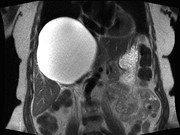

Single-incision laparoscopic management of a giant hepatic cyst

Kaitlin Willems and others

Journal of Surgical Case Reports, Volume 2015, Issue 7, July 2015, rjv073, https://doi.org/10.1093/jscr/rjv073